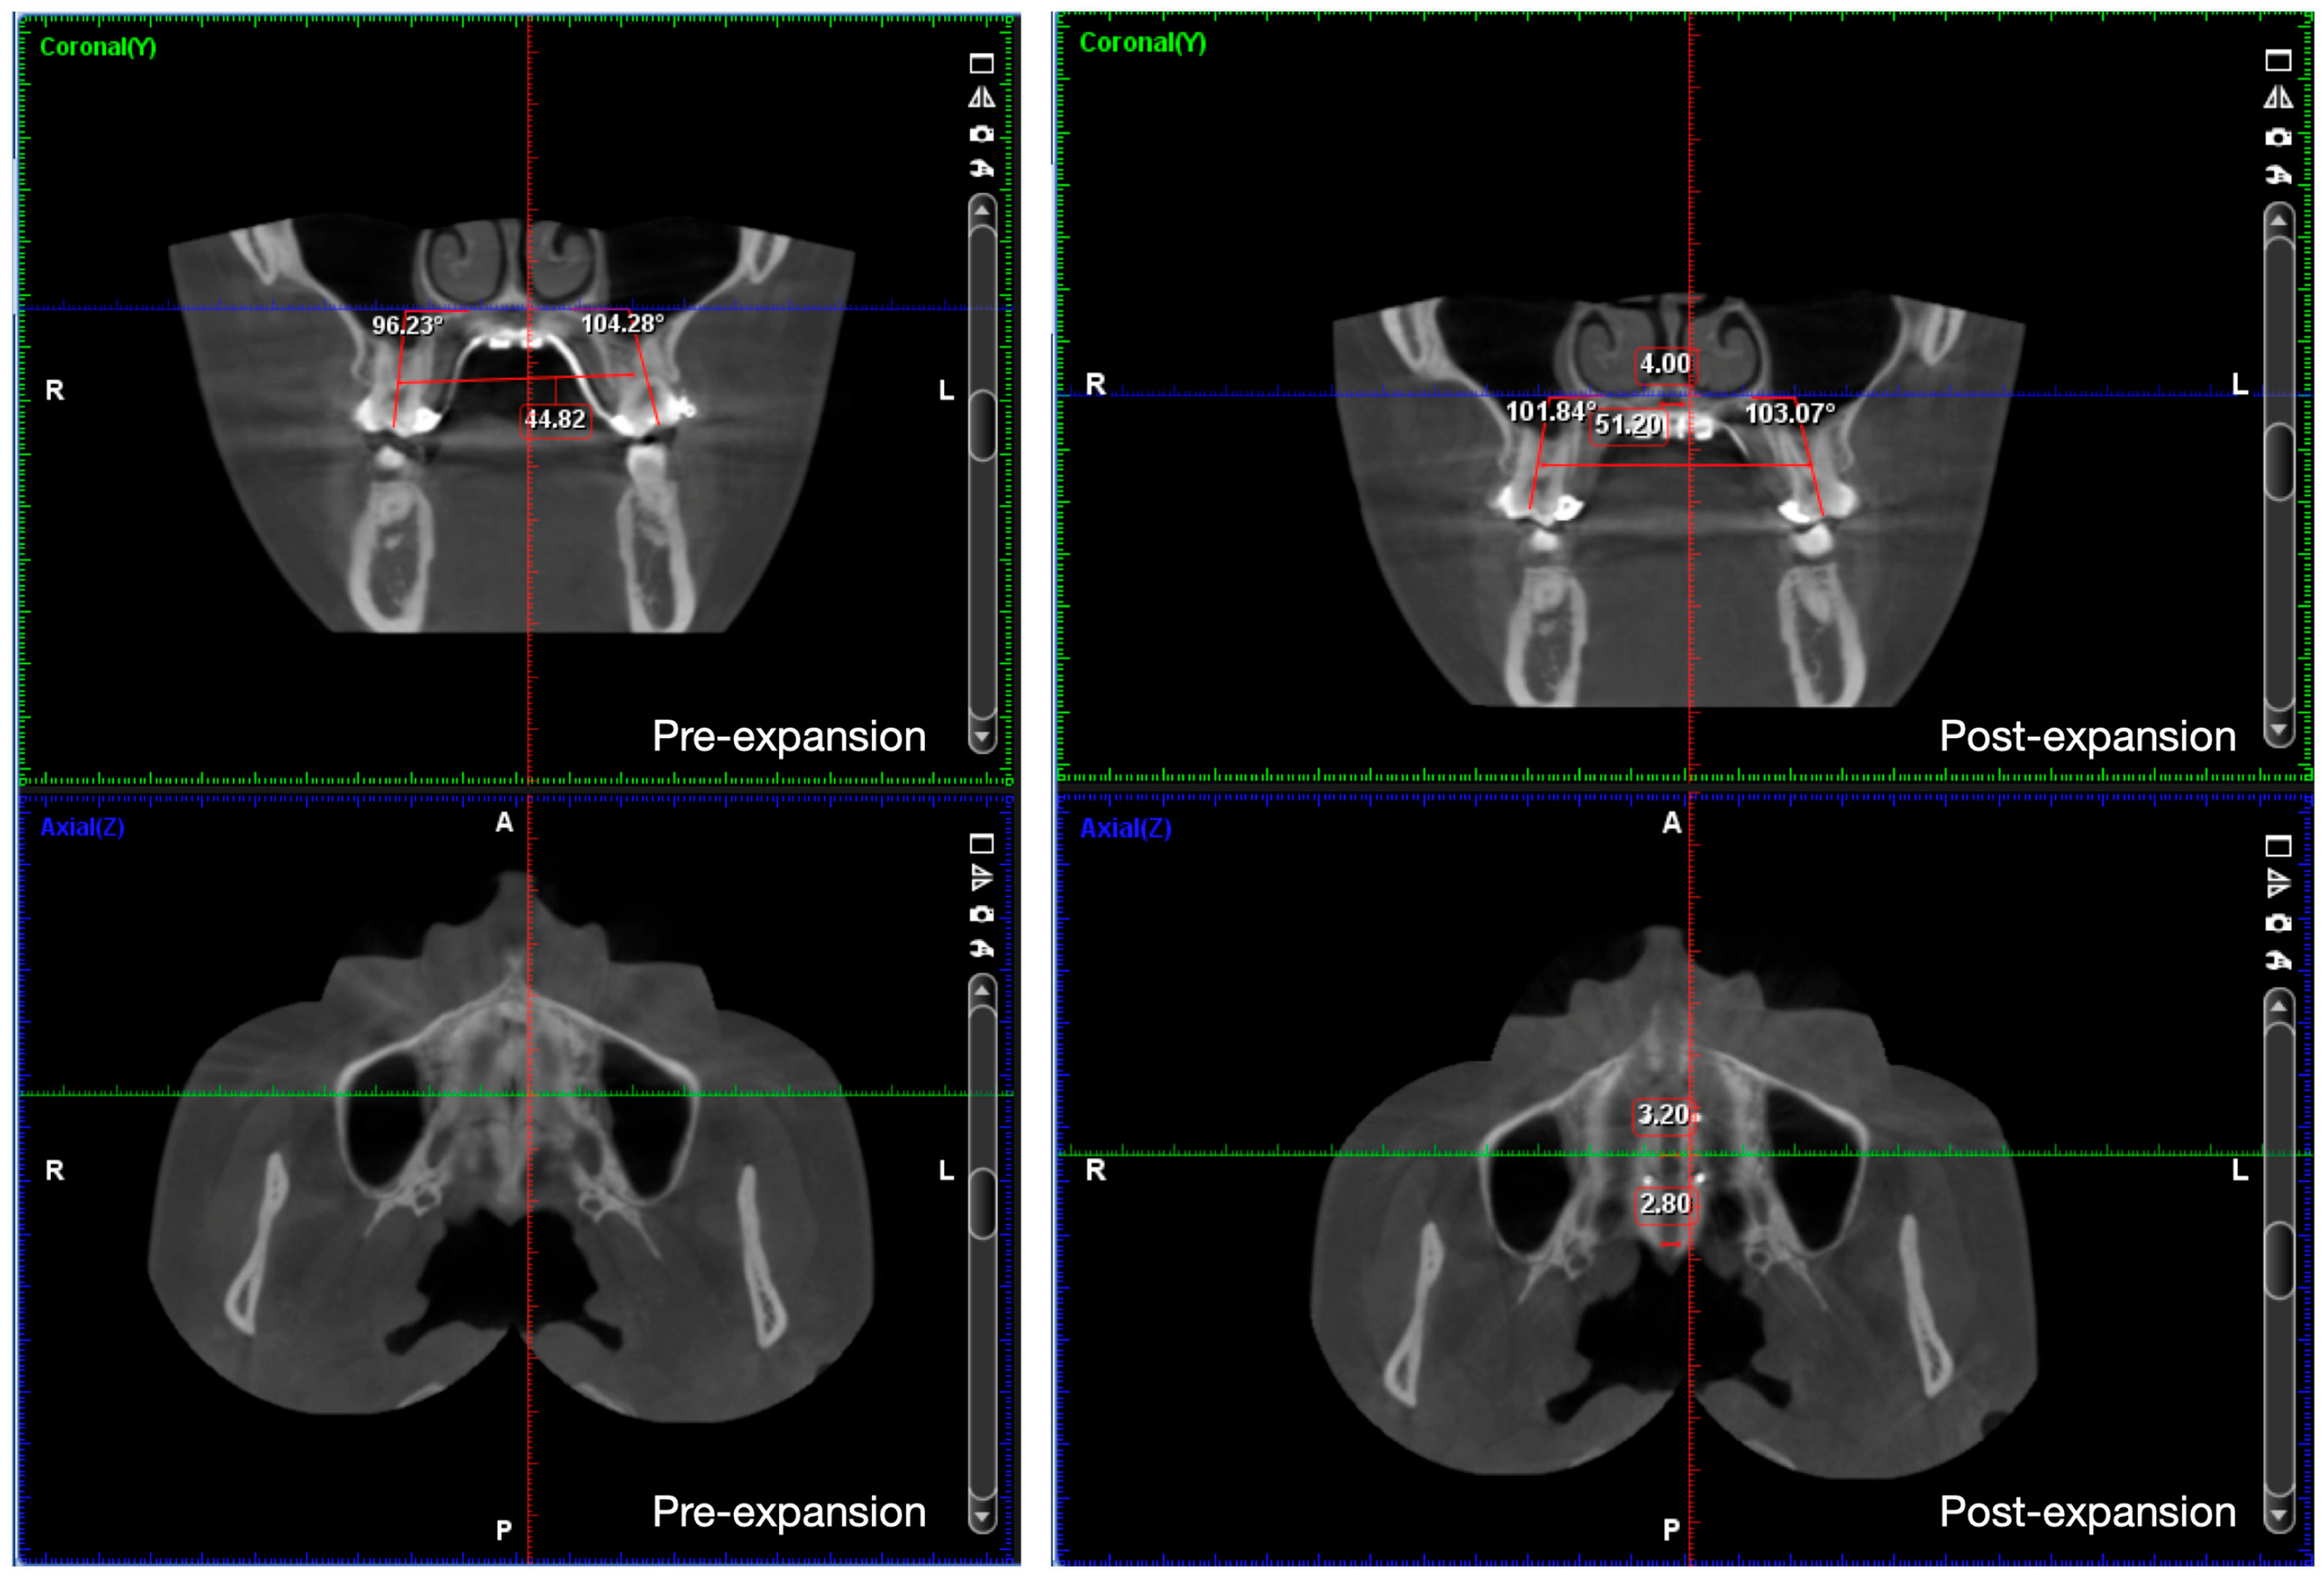

2.4. Treatment Progress

- Liao, Y.C.; Ho, K.H.; Wang, C.W.; Wang, K.L.; Hsieh, S.C.; Chang, H.M. Skeletal and dental changes after microimplant-assisted rapid palatal expansion (MARPE)—A Cephalometric and Cone-Beam Computed Tomography (CBCT) study. Clin. Investig. Orthod. 2022, 81, 84–92. [Google Scholar] [CrossRef]

- Song, K.T.; Park, J.H.; Moon, W.; Chae, J.M.; Kang, K.H. Three-dimensional changes of the zygomaticomaxillary complex after mini-implant assisted rapid maxillary expansion. Am. J. Orthod. Dentofac. Orthop. 2019, 156, 653–662. [Google Scholar] [CrossRef]